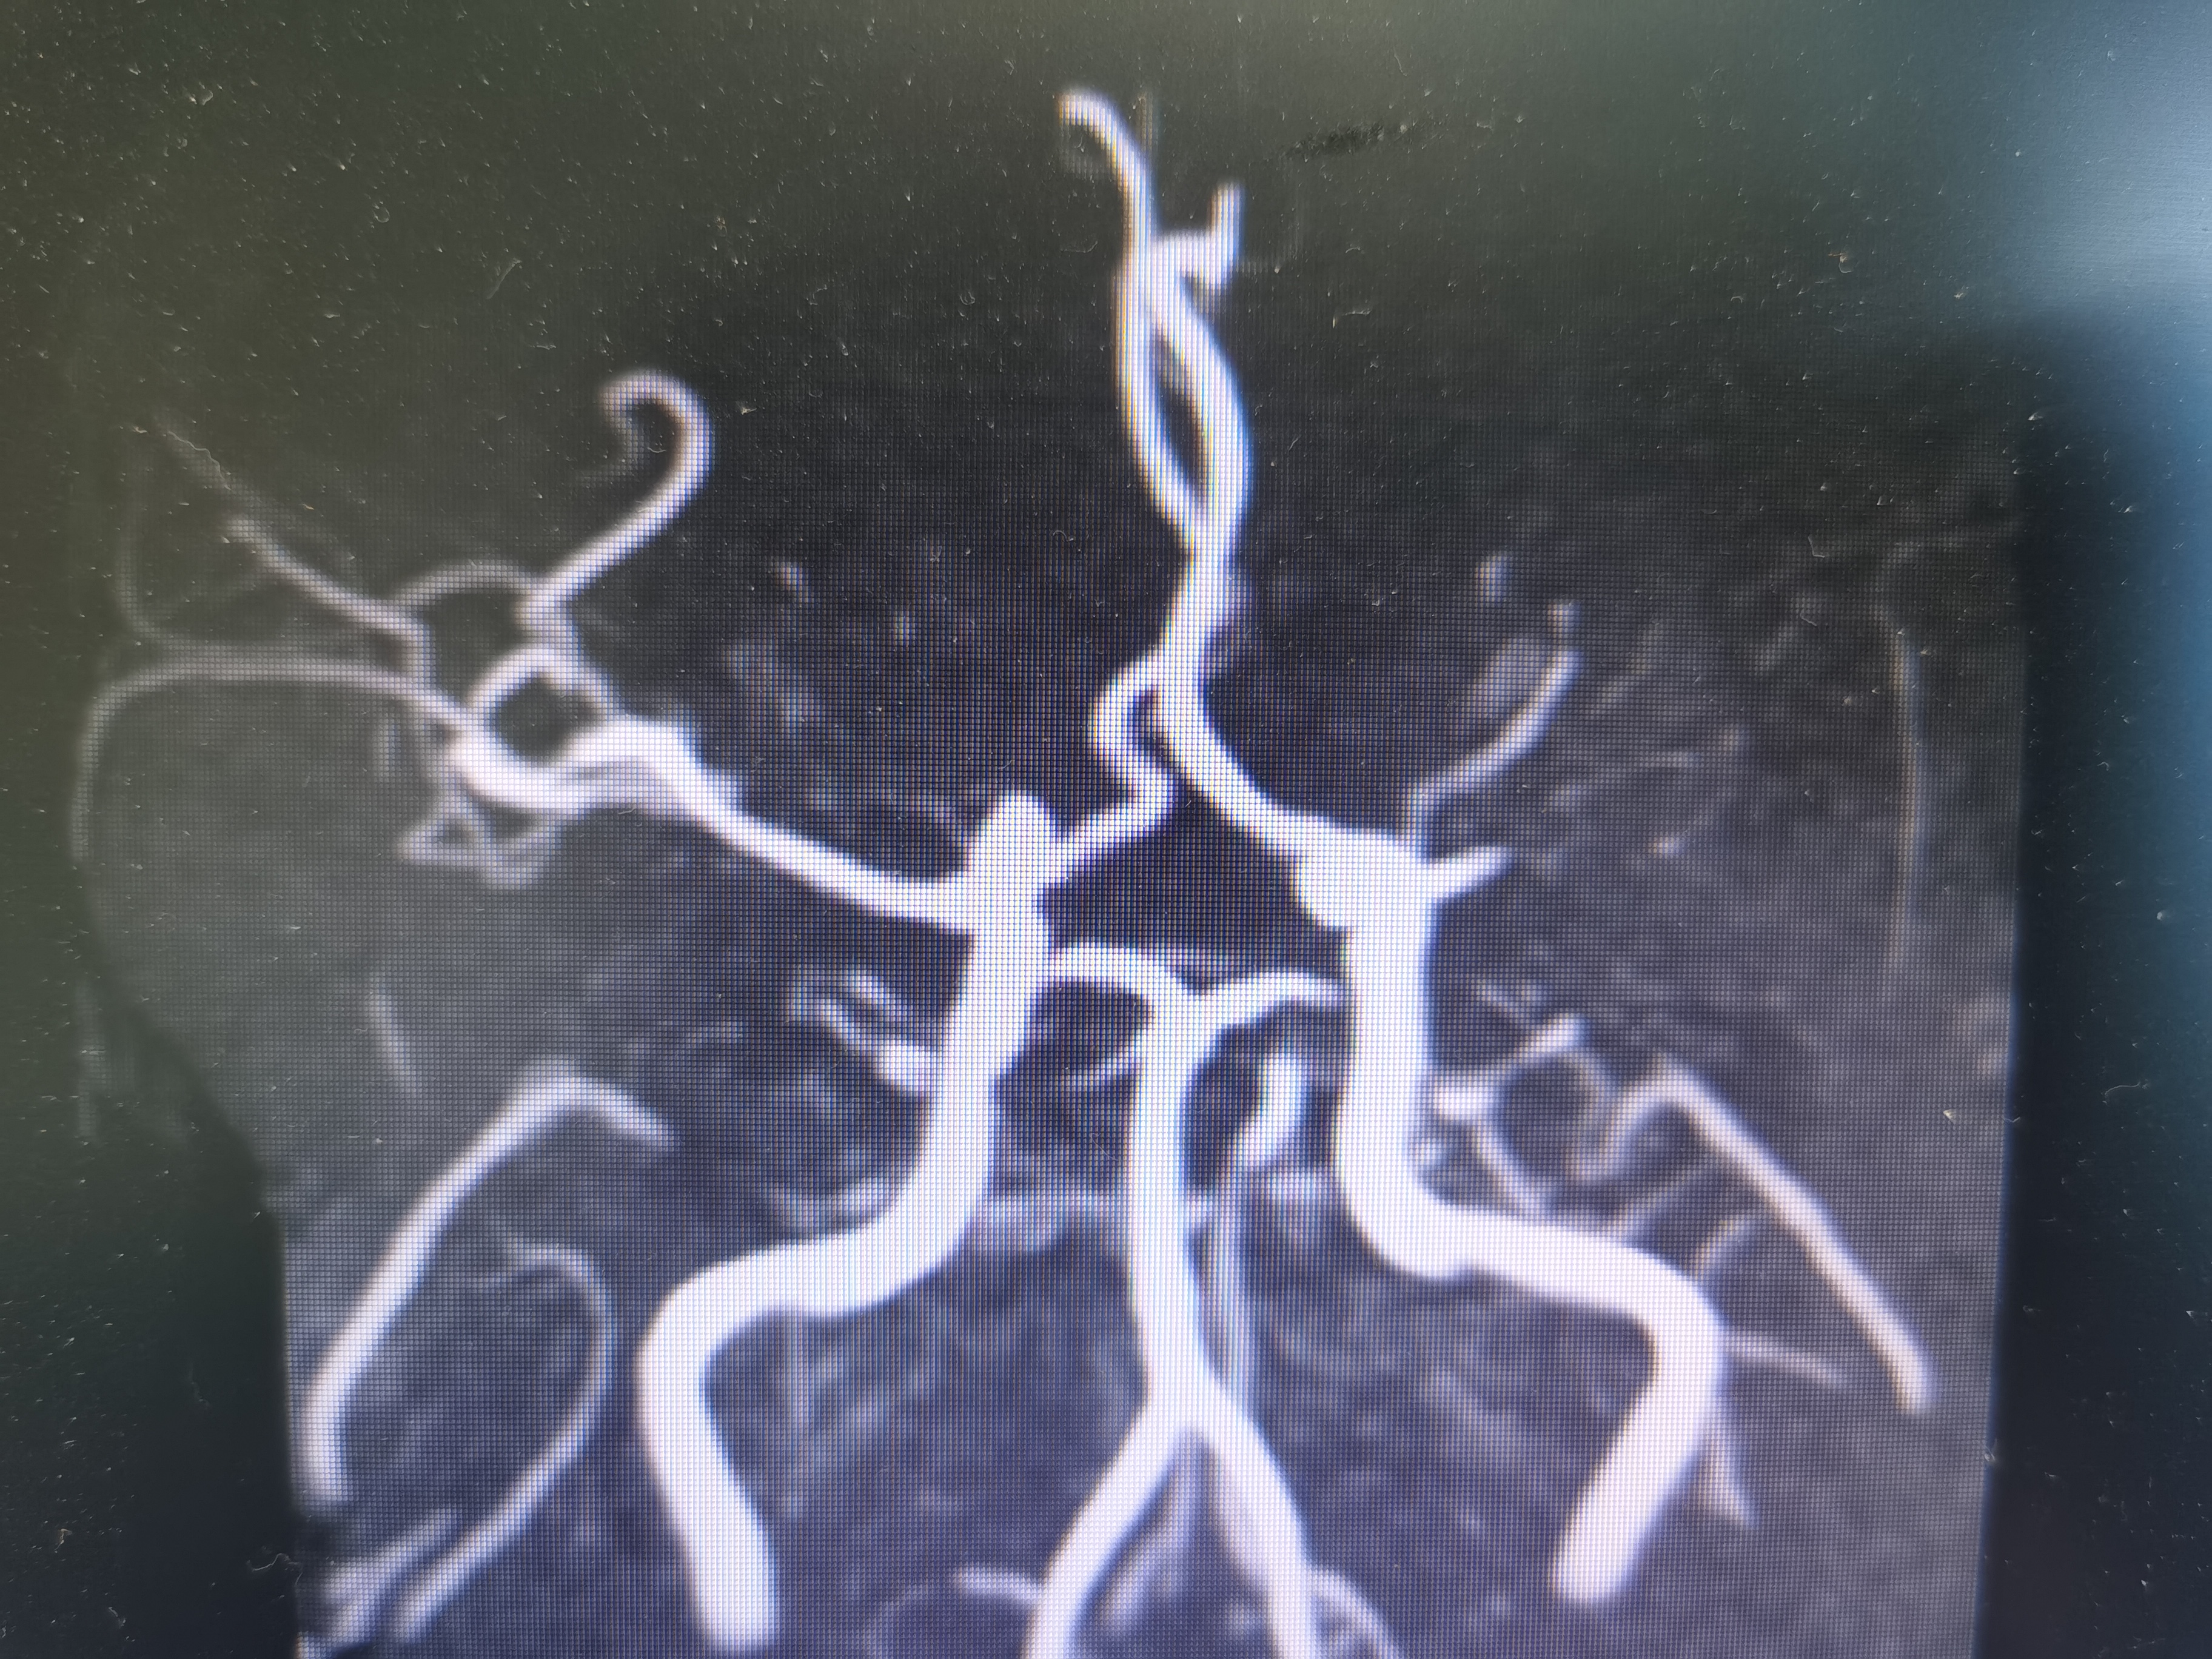

右椎动脉显影正常。

左侧大脑后动脉局部狭窄。

基底动脉显影正常。

左椎动脉显影正常。

右颈内动脉颅外段正常。

右颈内动脉颅内段显影正常。

右侧大脑中动脉M2局部狭窄。

左颈内动脉颅外段正常。

侧位见左侧大脑中动脉闭塞。

晚期可见左侧大脑中动脉返流。

正位见左侧大脑中动脉闭塞。

动脉晚期可见左侧大脑中动脉M2段返流。

造影分析:

患者左侧大脑中动脉M1起始段闭塞,动脉晚期可见返流至M2显影,考虑新近闭塞,具备介入开通指征,手术风险在于血管夹层,破裂及急性血栓形成,向患者家属详细交代病情后,家属积极要求介入治疗。